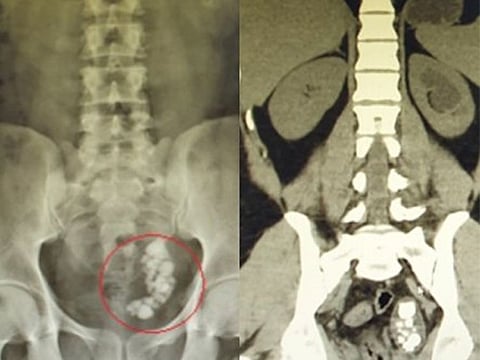

A detailed investigation, with an x-ray and an ultrasound, found that he had developed multiple stones blocking his ureter, ranging from eight to 22 millimetres in size.

Dr Hussain then opted to remove the stones by first breaking them with laser therapy.

“The patient has a rare congenital disorder of dilated lower ureter, called ureterocele, which causes swelling of the ureter. But in this case, he had an even rarer condition of a swollen ureter blocked by multiple stones.”